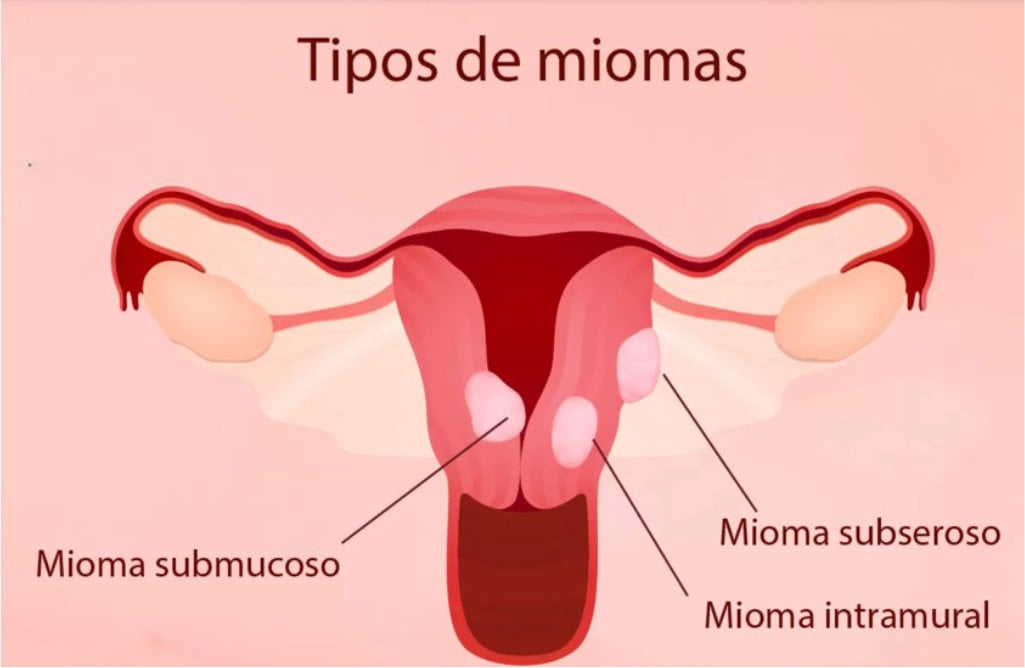

CLASSIFICAÇÃO:

Os miomas podem ser classificados em: submucosos, intramurais e subserosos de acordo com a relação com endométrio (camada interna), miométrio (camada muscular e intermédia) e serosa(camada mais externa uterina).